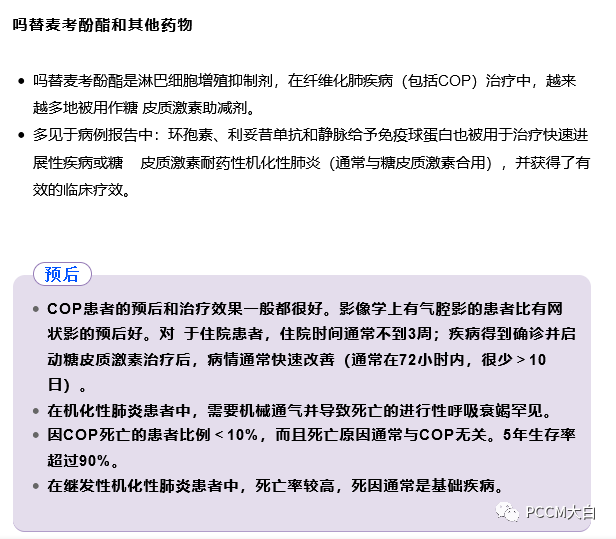

其他治疗

初始使用全身糖皮质激素治疗无效或糖皮质激素不能减至安全剂量,可以考虑使用替代药物。

大环内酯类抗生素

病例报告和小规模回顾性病例研究提示,在COP患者中,具有抗炎特性的大环内酯类抗生素(如红霉素或克拉霉素)可作为口服糖皮质激素的辅助方案或替代方案。

大环内酯类抗生素通常用药3~6个月或更长时间,并在停止治疗期间密切监测,以防复发。大环内酯类药物单独使用效果不佳,且适当的剂量和持续时间有待确定。

硫唑嘌呤或环磷酰胺

硫唑嘌呤或环磷酰胺不推荐用于COP患者,只有其他疗法均失败的极少数情况例外。

对于肾功能正常的患者,硫唑嘌呤的起始剂量为每日1~2mg/kg(每日1次口服),最大剂量为每 日150 mg。建议从每日50 mg的剂量开始,在2~4周期间缓慢增加剂量,治疗持续至少3个月。

考虑到环磷酰胺的相关毒性作用,应在6个月后停药。